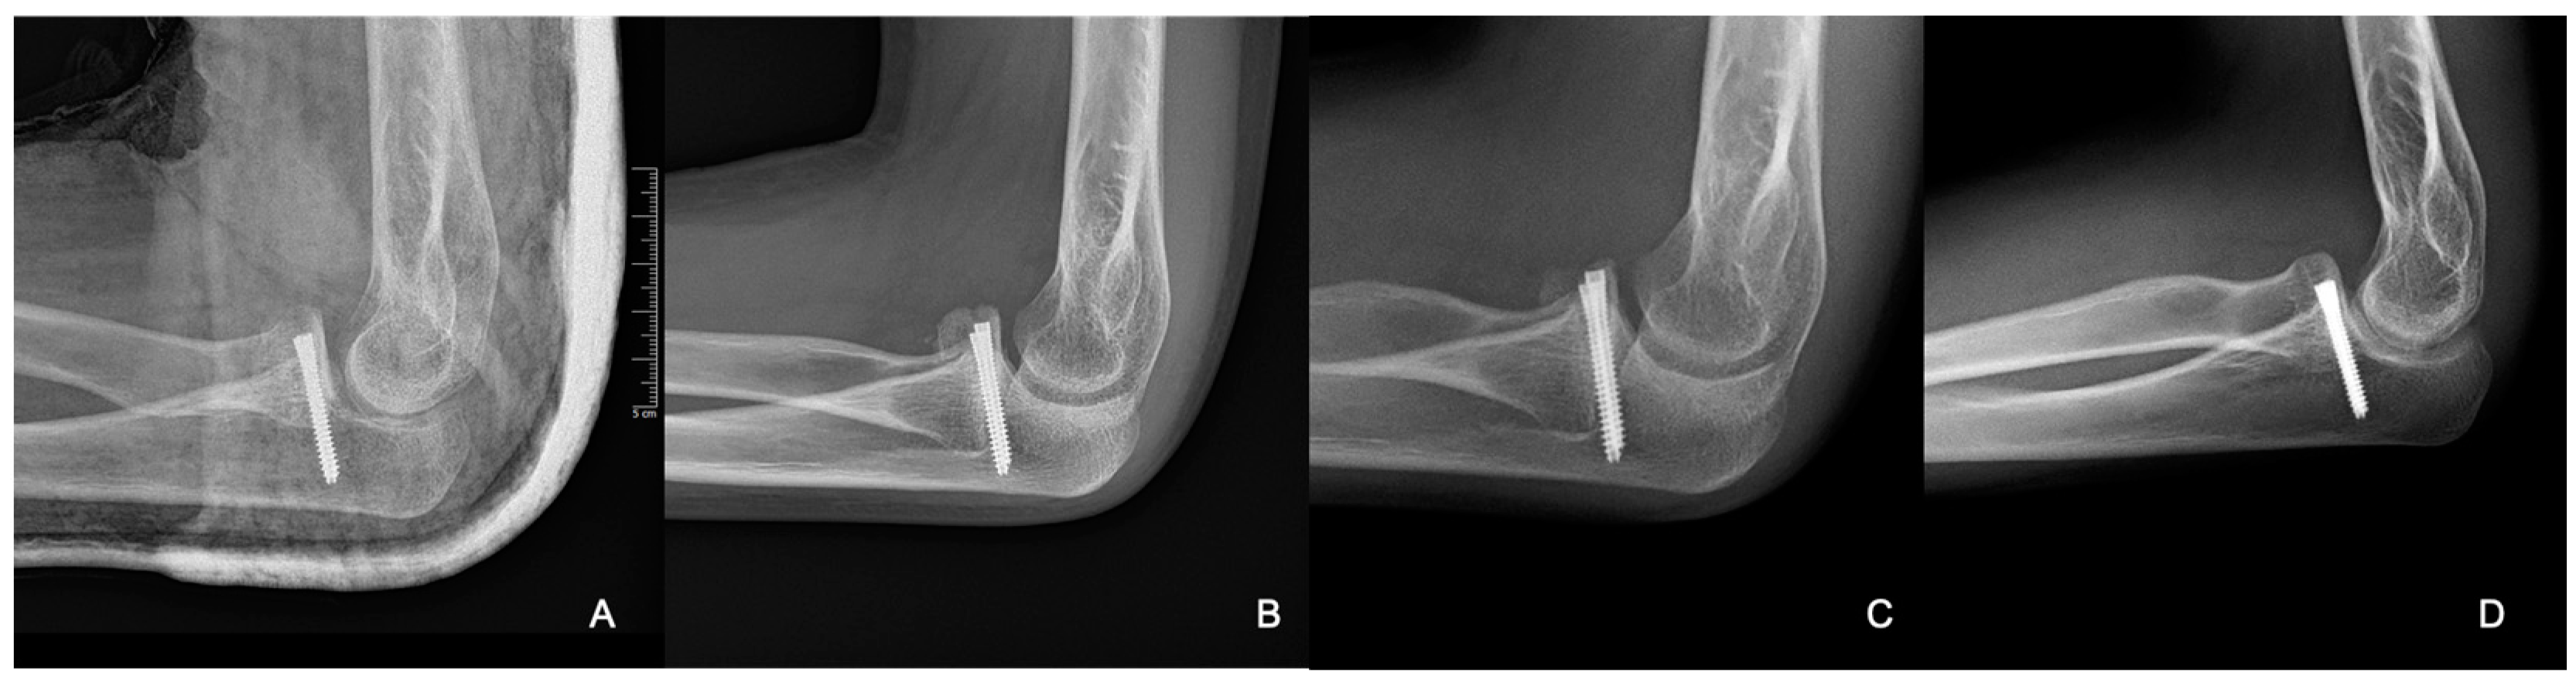

An 11-year-old girl reported to our infirmary on the 10 October 2020 with recurrent posterior subluxation of the elbow. The patient’s history described a previous injury in 2017 when she jumped from a swing and ended up injuring her left elbow (Figure 1). This luxation injury was reduced and treated conservatively with a cast for six weeks. In 2018, she suffered another injury on the same extremity, which was treated the same way. In April 2019, her elbow dislocated three times in a single day, so a cast was applied for seven weeks, and X-rays and CT scans were performed.

Figure 1. Plain radiographs taken at the initial injury.

Figure 8. Radiographic control images from weeks 3 (A), 8 (B), 24 (C), and 40 (D).